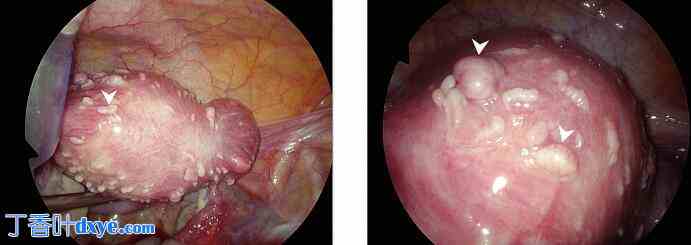

腹腔镜探查时,发现子宫体积增大,内有多个子宫肌瘤。前壁子宫肌瘤包括一个 4 x 4 厘米的壁内 FIGO 3 型子宫肌瘤和一个 3 x 2 厘米的 5 型子宫肌瘤,位于左侧输卵管附近。此外,在子宫前后壁上均发现多个小的幼苗状病变。这些病变与可能在先前宫腔镜子宫肌瘤切除术后出现的寄生性子宫肌瘤相符。对这些病变进行了活检,然后切除并电灼治疗。组织病理学证实这些病变为良性平滑肌瘤(寄生性子宫肌瘤)(图 3、图 4)。

图 3.

腹腔镜子宫图像显示子宫表面多发性播散性平滑肌瘤病或寄生性子宫肌瘤,箭头所示。